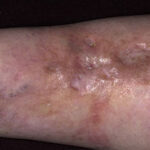

Classically, NL presents with one to several sharply demarcated yellow-brown plaques on the anterior pretibial region . The lesions have a violaceous, irregular border that may be raised and indurated. Initially, NL often presents as red-brown papules and nodules that may mimic sarcoid or granuloma annulare (GA). Over time, the lesions flatten, and a central yellow or orange area becomes atrophic, and commonly telangiectasias are visible, taking on the characteristic “glazed-porcelain” sheen. Aside from the shins, other sites of predilection include ankles, calves, thighs, and feet. Fifteen percent of patients develop lesions on the upper extremities and trunk that tend to be more papulonodular. Although pain and pruritus have been reported, most lesions are asymptomatic. Anesthesia of the plaques does occur.

The clinical course is often indolent, with spontaneous remission in less than 20 percent of cases. Over time, the plaques tend to stabilize, and formation of new lesions tapers off. However, the possibility of ulceration, a poor spontaneous remission rate, and cosmetic concerns lead patients to seek treatment. Ulceration, the most serious complication, occurs in approximately 13 percent to 35 percent of cases on the legs. A few cases of squamous cell carcinoma arising in chronic ulcerative lesions of NL have been reported. Multiple reports document the association of NL with GA and sarcoidosis.